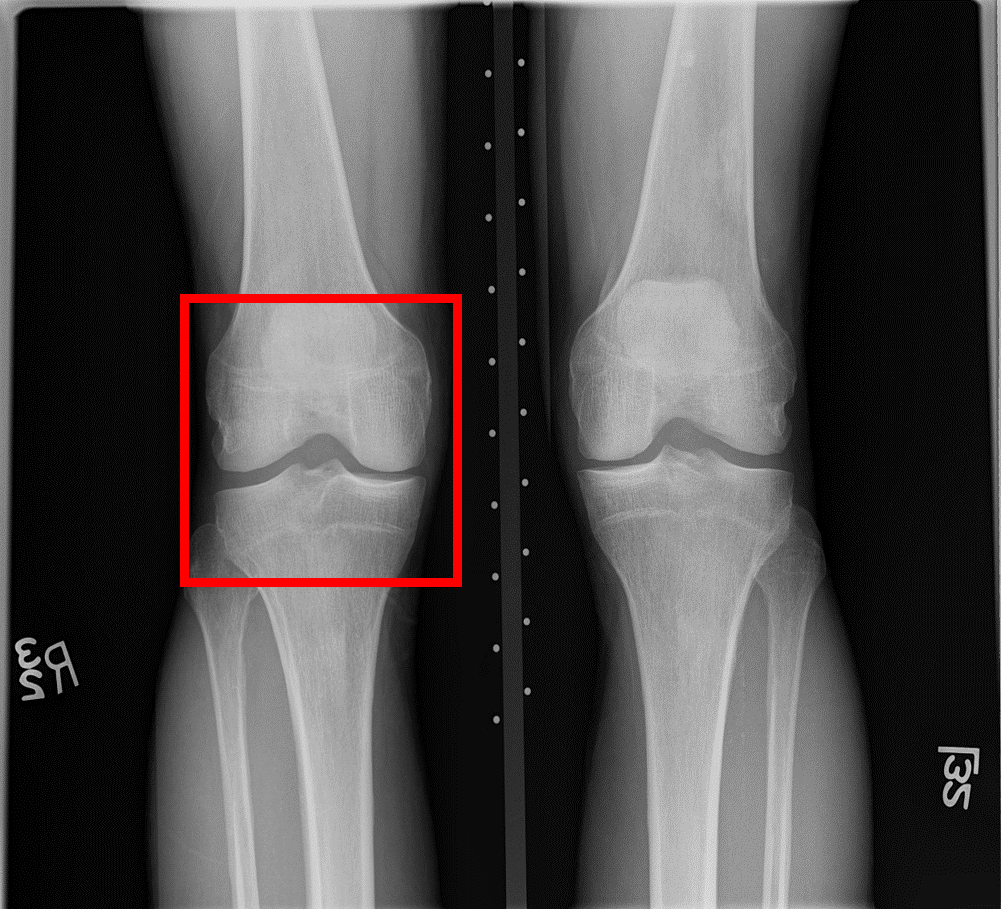

3.2 Data preprocessing

The knee joints employed in this study are derived from [34]. As shown in Fig. 3, the knee joint (Fig. 3(b)) was identified from the plain radiograph (Fig. 3(a)) through the YOLOv2 learning model [35], with images sized 299 ×\times 299, which were resized to 224×\times224 pixels, and image intensity was normalized to [-1, 1]. As a result of the preprocessing steps, 60 pairs of KL-0 and KL-4 images were collected from the baseline, 24-month, 36-month, 48-month, 72-month, and 96-month datasets. Each X-ray image pair was obtained from the same patient, ensuring consistency in the temporal progression of KOA within the dataset.

Refer to caption

(a) A standard knee plain radiograph

(b) An identified knee joint

Figure 3: A standard knee plain radiograph from the database and an identified knee joint highlighted in a red box 3(a). An identified knee joint 3(b).